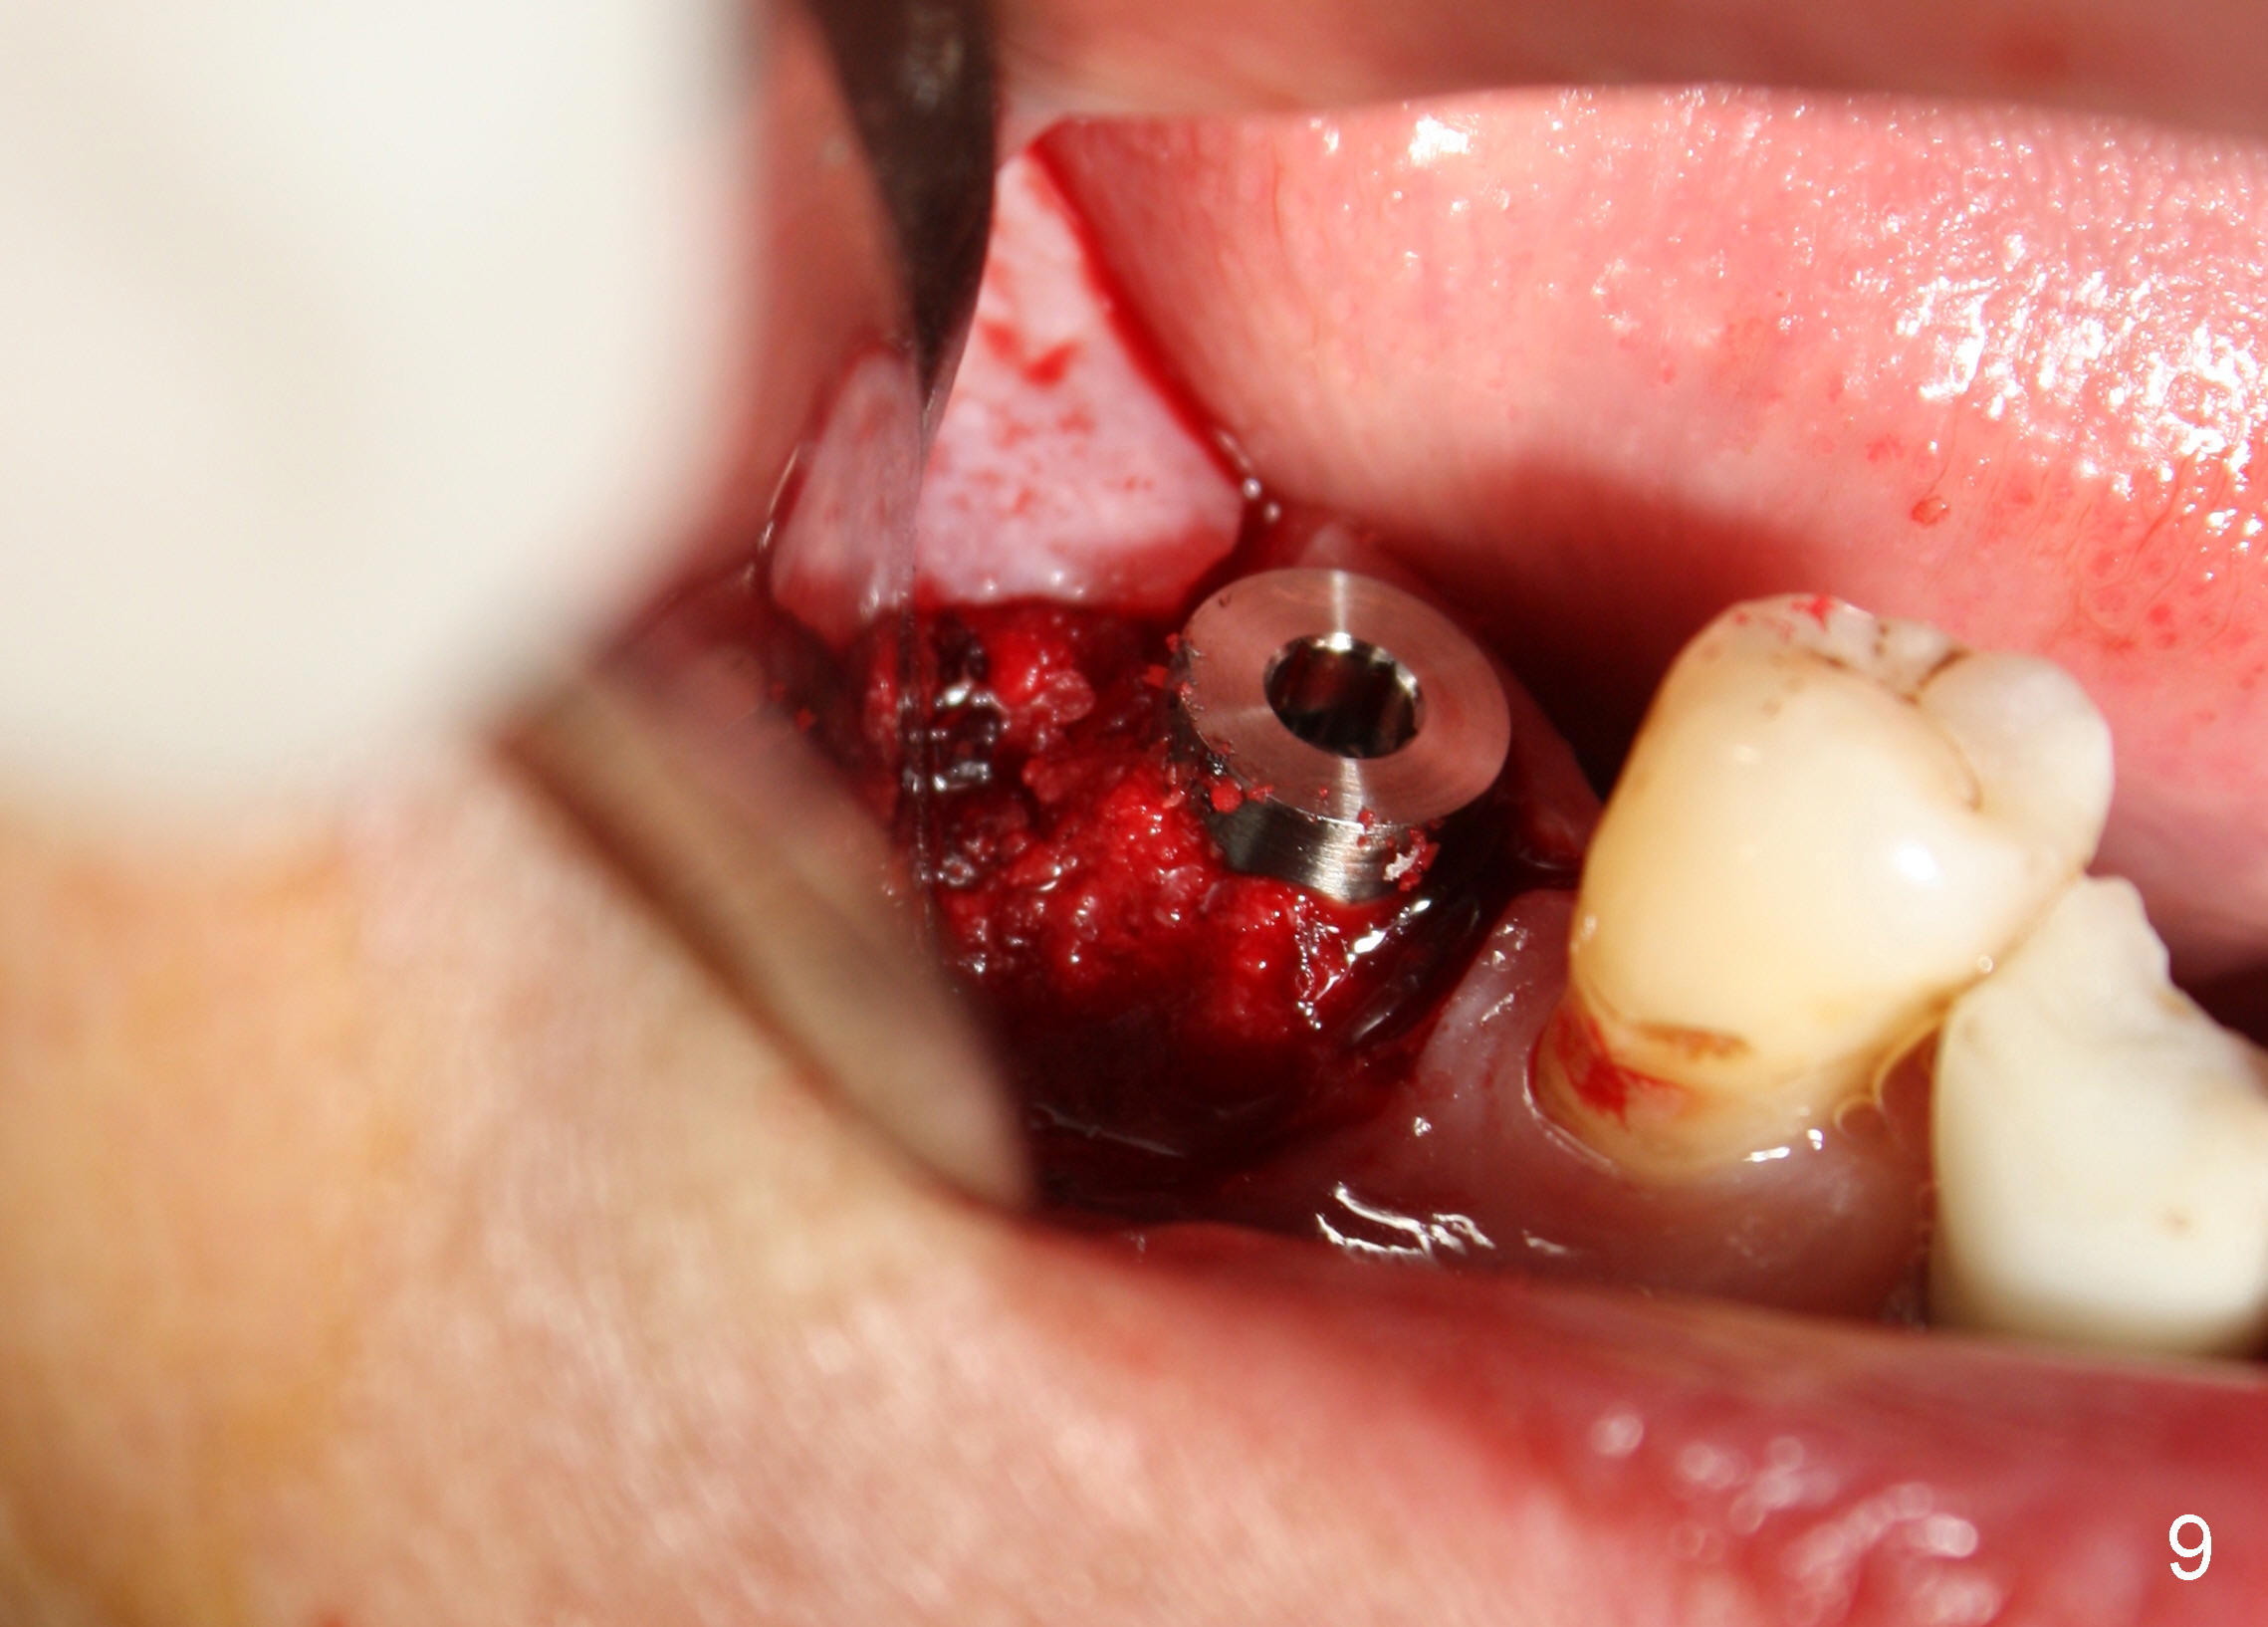

CBCT studies show that a 6x11 mm implant can be safely placed at the site of the tooth #30 (Fig.1 (coronal), 2 (sagittal section). Osteotomy is initiated by 2 mm pilot drill at the depth of 8 mm from the crest (the prospective implant is 3 mm above the crest); X-ray is taken with a parallel pin (Fig.3 P). It appears that there is 12 mm of bone from the crest to the upper border of the inferior alveolar nerve canal. The depth of osteotomy is accordingly adjusted to 11 mm below the crest; osteotomy finishes with insertion of 6x14 mm tap (Fig.4); the patient feels pressure while the tap is being inserted. Following further infiltration with Lidocaine, the depth of the osteotomy is intended to increase in order to bury the implant deeper, because the coronal portion of the buccal plate starts to perforate. The patient feels pain. Finally a 6x14 mm implant is placed ~ 1 mm above the inferior alveolar canal (Fig.5). As mentioned earlier, the rough surface of the implant is exposed buccally (Fig.6 between arrowheads). The nearby buccal plate is decorticated (Fig.7). The autogenous bone harvested during osteotomy (Fig.8) is going to be placed over the exposed portion of the rough surface of the implant (Fig.9); the graft is covered by collagen dressing (Fig.10). The buccal and lingual flaps are approximated with sutures mesial and distal to the implant (Fig.11). To increase the retention of perio dressing, a 4x3 mm abutment is placed.